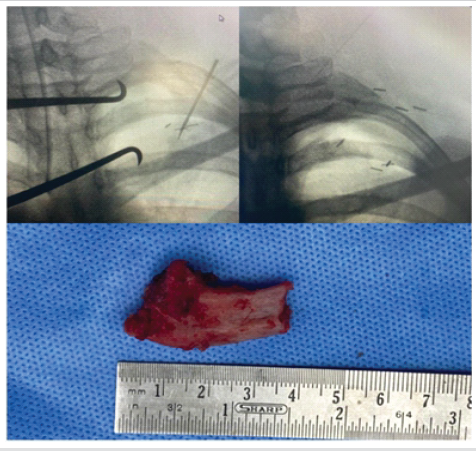

Due to progressive symptoms and radiological evidence of compression, surgical intervention was planned. The patient underwent left brachial plexus exploration, anterior scalenectomy, first rib excision through supraclavicular approach, and pectoralis minor tendon tenotomy (PMT). The patient is positioned supine with a shoulder roll to facilitate neck extension, and the head is rotated to the contralateral side. A transverse or oblique incision is placed approximately 1–2 cm superior to the clavicle. After division of the platysma, the supraclavicular fat pad is mobilized, with careful identification and preservation of the supraclavicular nerves. The phrenic nerve is identified along the anterior scalene muscle and protected throughout the procedure. Scalenectomy was performed as indicated, followed by exposure of the brachial plexus trunks, allowing neurolysis. Intraoperatively, it was found that the fibrosis and bony irregularity around the first rib contributed to narrowing of the costoclavicular space, which resulted in the compression of the neurovascular structures. Following excision of the first rib, the compression was released at the costoclavicular junction. Through deltopectoral approach, identification and division of the pectoralis minor at the insertion of the coracoid process, and surgical decompression of the infraclavicular portion of the brachial plexus was done. Throughout the procedure, the brachial plexus motor integrity was checked with a nerve stimulator and was found to be intact (Fig. 4,5,6,7). Histopathology of the excised rib showed fibrocartilage and bony fragments with areas of fibrosis and congestion.

Figure 6: Intraoperative C-arm images showing part of the first rib before and after excision at the costoclavicular junction and the excised portion of the first rib.